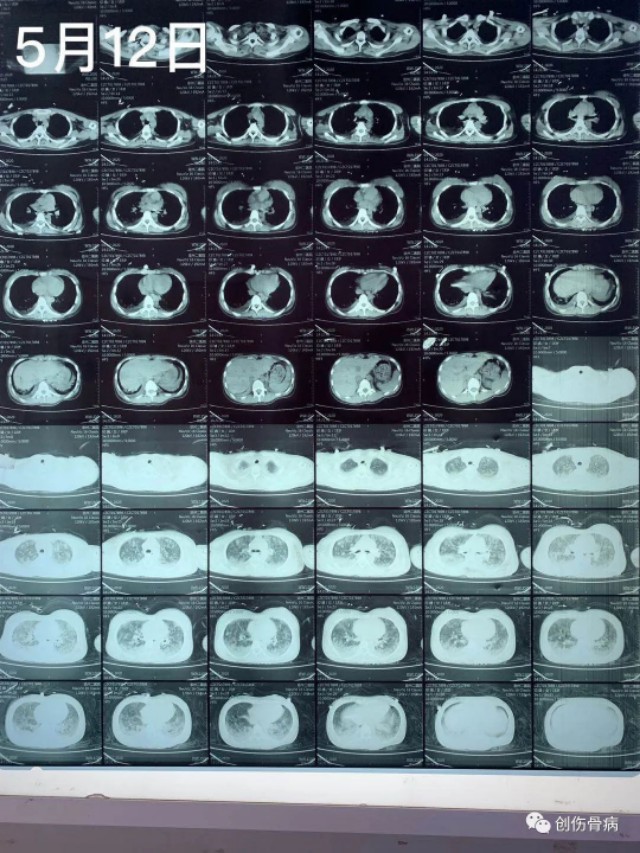

都说车祸无情,但是创伤后的并发症也仍然无情。2020年5月9日21时55分我科室接收一名18岁外伤小妹妹,当天晚上小妹妹跟爸爸妈妈路边漫步被一汽车撞倒受伤,送至我院时就是一单纯右胫腓骨下段粉碎性骨折伴头皮裂伤,入院行右小腿DR及胸部CT示:2020年5月12日14时左右,小妹妹突然出现呼吸困难、烦躁不安,氧饱和度40-50%,家属诉小女孩昨日夜间有偷偷咳嗽的表现,当班医生一看就考虑脂肪栓塞立即给与安排行胸部CT示:

2020年5月12日14时左右,小妹妹突然出现呼吸困难、烦躁不安,氧饱和度40-50%,家属诉小女孩昨日夜间有偷偷咳嗽的表现,当班医生一看就考虑脂肪栓塞立即给与安排行胸部CT示:随后转入ICU气管插管、呼吸机控制呼吸、激素冲击、抗炎、脑康复等抢救治疗,短时间内出现急性肺水肿,气管插管内全是粉红色泡沫痰,恰逢月经期,各种用药都存在矛盾,血色素也直线下降,对于此类病人外界压力也挺大的,有说希望渺茫的,有说必死无疑的,也有建议转院治疗的。。。。。好在家属比较理解也比较信任我们,给予对症抢救治疗4天、13天后复查胸部CT示: